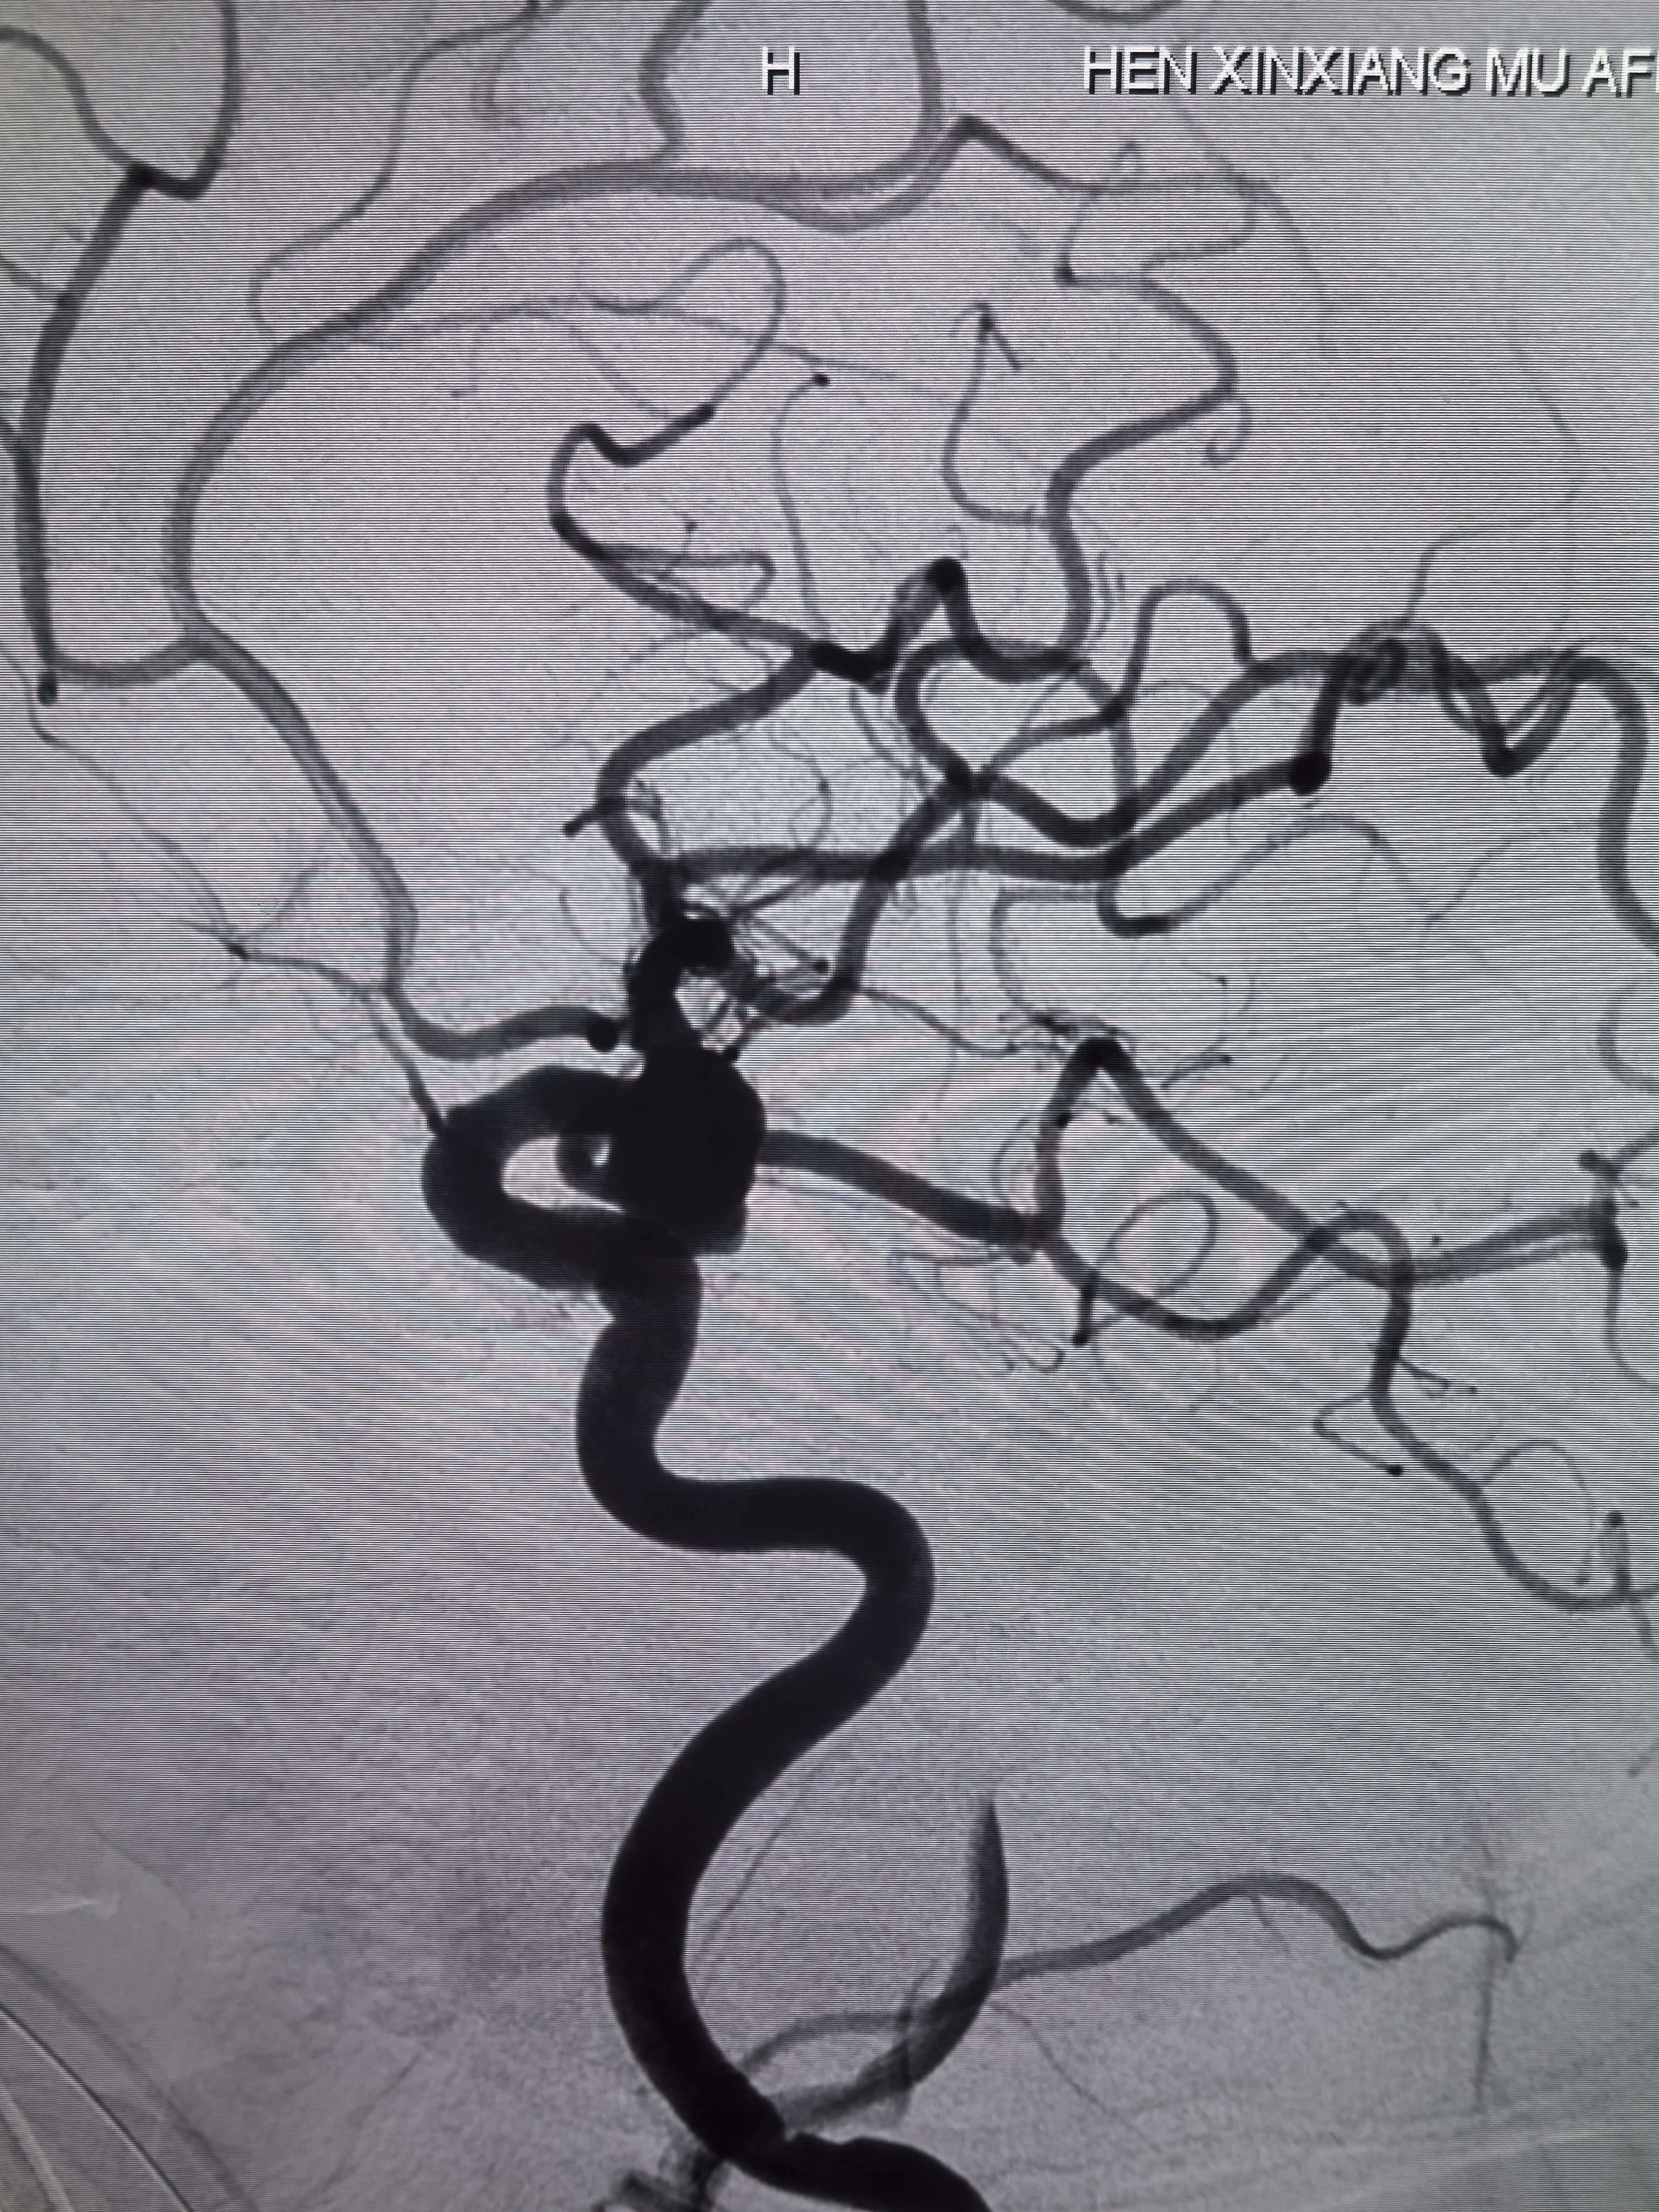

三维旋转造影!

三维重建,胚胎型大脑后动脉发自瘤体侧壁,超选困难且风险大!